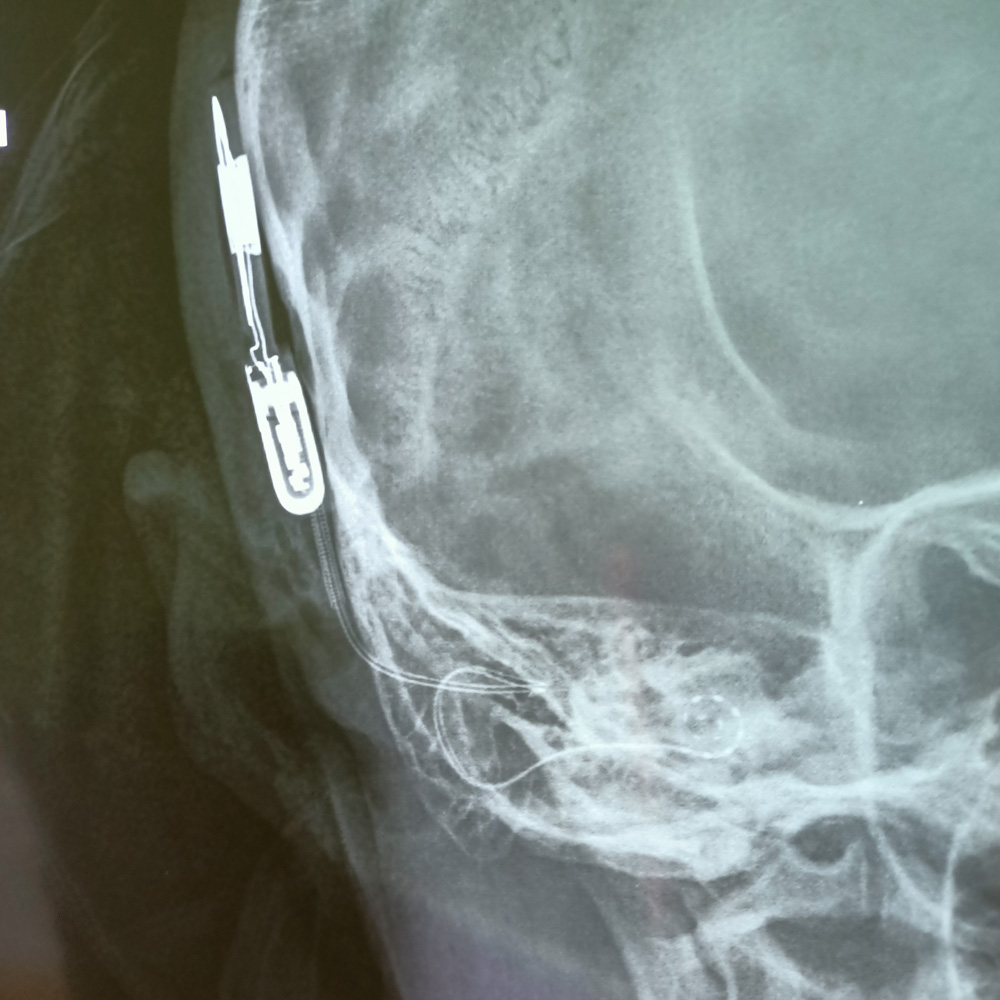

WAS GENAU IST EIN COCHLEA-IMPLANTAT?

Das Cochlea-Implantat (engl. cochlear implant, CI) ist eine Hörprothese für Gehörlose, deren Hörnerv noch funktioniert. Das CI-System besteht aus einem Mikrofon, einem digitalen Sprachprozessor, einer Sendespule mit Magnet, und dem eigentlichen Implantat, das sich aus einem weiteren Magneten, einer Empfangsspule, dem Stimulator und dem Elektrodenträger mit den Stimulationselektroden zusammensetzt. Die Elektroden werden in die Cochlea (Hörschnecke) eingeführt. Die Empfangsspule wird hinter dem Ohr unter der Haut platziert. Die Sendespule des Prozessors haftet mit Hilfe der Magneten auf der Kopfhaut über der Empfangsspule des Implantats. Die Spannungsversorgung des Implantats erfolgt durch die Kopfhaut mittels elektromagnetischer Induktion. Die Signalübertragung erfolgt mit Hochfrequenzwellen. Manchmal wird nur das Elektrodenbündel als CI, die komplette Anlage als CI-System bezeichnet.